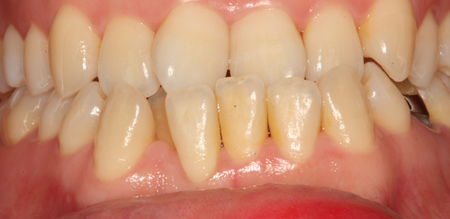

치주치료 전후사진

B

A

치은염 (초기~중기)

치아 주위의 잇몸이 붉게 부어 있으며, 칫솔질 등을 할 때 피가 남.

스케일링 주기의 조절이 필요할 수 있으며, 올바른 칫솔질을 시행하여야 함.

치주염 (중기~말기)

주기적으로 잇몸이 붓고 피가 나며, 욱씬하거나 우리한 통증이 나타남.

치주치료 및 정도에 따라 치주수술(잇몸수술)이 필요함. 향후 관리 정도에 따라 3~6개월 간격으로 내원하여 유지치료를 시행하여야 함.

치주염 (말기)

잇몸이 항상 부어 있으며, 이가

흔들리는 정도가 점점 심해짐.

치주치료가 필요하며, 정도에 따라 치아를 발치하여야 할 수 있음.